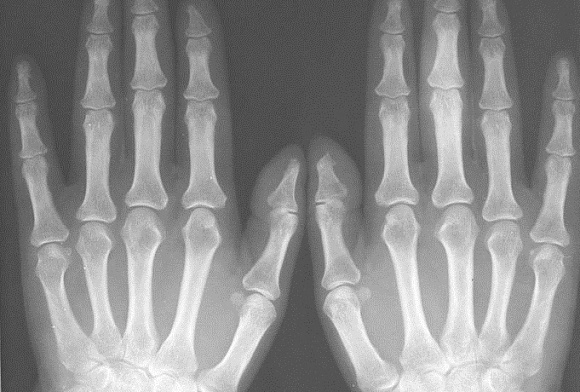

Рентген кисти рук

Чтобы выяснить состояние костно-мышечной системы верхних конечностей, травматолог или ортопед назначает пациенту рентген кисти руки.

Цена исследования невысока, выполняется оно очень просто и быстро, поэтому при травмах и заболеваниях рук рентгеновские снимки, как правило, становятся основной диагностической процедурой.

С их помощью лечащий врач выявляет патологические изменения, которые невозможно обнаружить при визуальном осмотре, и выбирает схему лечения, которая быстрее и эффективнее прочих позволит восстановить функции кисти и запястья.

• Что показывает рентген кисти рук?

Опытный рентгенолог выявляет на снимках практически любые патологические изменения костных структур и мягких тканей, в том числе:

• кисты (полостные опухоли доброкачественного характера);

• синовиты (жидкость в суставах);

• теносиновиты (воспаления сухожилий);

• кальцификаты и остеофиты;

• признаки остеопороза;

• переломы, трещины, вывихи, ушибы и другие травматические повреждения.